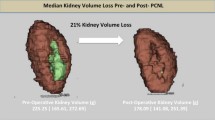

Three-dimensional models of renal stones were constructed successfully for all 15 patients. The integrated 3D model of renal stones accurately represented the actual size of the kidney and its anatomical landmarks. By adjusting the transparency of the kidney, intrarenal arteries, veins, and collecting system with the stones were clearly visualized. The number of stones, location of the collecting system, and dilation of the renal calyces were clearly visible. The interrelationships between the kidney and adjacent anatomical structures such as the spine, ribs, lungs, liver, and spleen were presented simultaneously. Preoperative comprehensive planning of PCNL was performed, and the puncture point and direction were planned before PCNL (Fig. 3).

With the aid of the 3D model, intraoperative PCNL was completed successfully in all 15 patients (Table 1). None of the patients required additional therapy. The mean stone volume was 11,591 ± 6,889 mm3, the mean operating time was 75.6 ± 13.4 min, and blood loss was 1.2 ± 0.3 g/l. No intraoperative complications occurred. The one-stage stone-free rate was 93.3 %. One of the patients required a second stage to clear a residual 6-mm stone. Two patients required two tracts (one for a 20F sheath and the other for a 16F) to clear stones on the basis of their preoperative plans. The final stone-free rate was 100 %. No postoperative complications were noted, except for postoperative pain in one patient (Clavien grade 1).